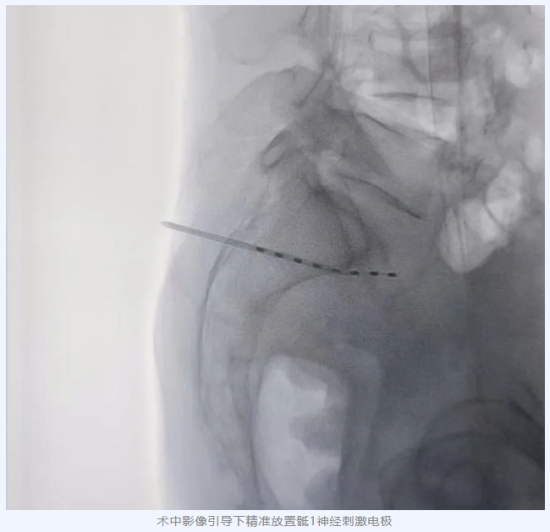

辗转问诊后,张大爷慕名来到哈医大四院疼痛科。面对这一棘手病例,周华成主任带领团队对其进行了全面细致的评估。结合患者疼痛的精确分布特征:从腰骶下部、臀、大腿后侧、小腿后外侧至足跟/足底外侧,及其特征性的神经病理痛表现,周主任锁定病根:骶1神经在病毒感染后发生了病理性功能紊乱,正是这“失控的开关”源源不断地向大脑发送剧烈的疼痛信号。不同于其他部位,累及骶神经根的疱疹后神经痛,因其疼痛区域深在、神经解剖结构复杂,传统治疗方法难以精准作用于深部的骶神经根,效果往往短暂或不佳。经过严谨讨论,团队决定为张大爷实施黑龙江省内首例精准定位的骶1神经电刺激(Sacral Nerve Stimulation, SNS)植入术。

在先进的影像设备引导下,周主任将微小的刺激电极精准植入到目标骶1神经的区域。当电刺激开启时,张大爷感觉疼痛显著缓解,原本剧烈的烧灼痛、电击感区域瞬间被舒适的酥麻感覆盖。电极植入的一周内:爆发痛的发作频次逐渐降低、持续时间逐渐缩短、疼痛程度逐渐减轻。拔除电极时,张大爷惊喜地发现疼痛消失了。